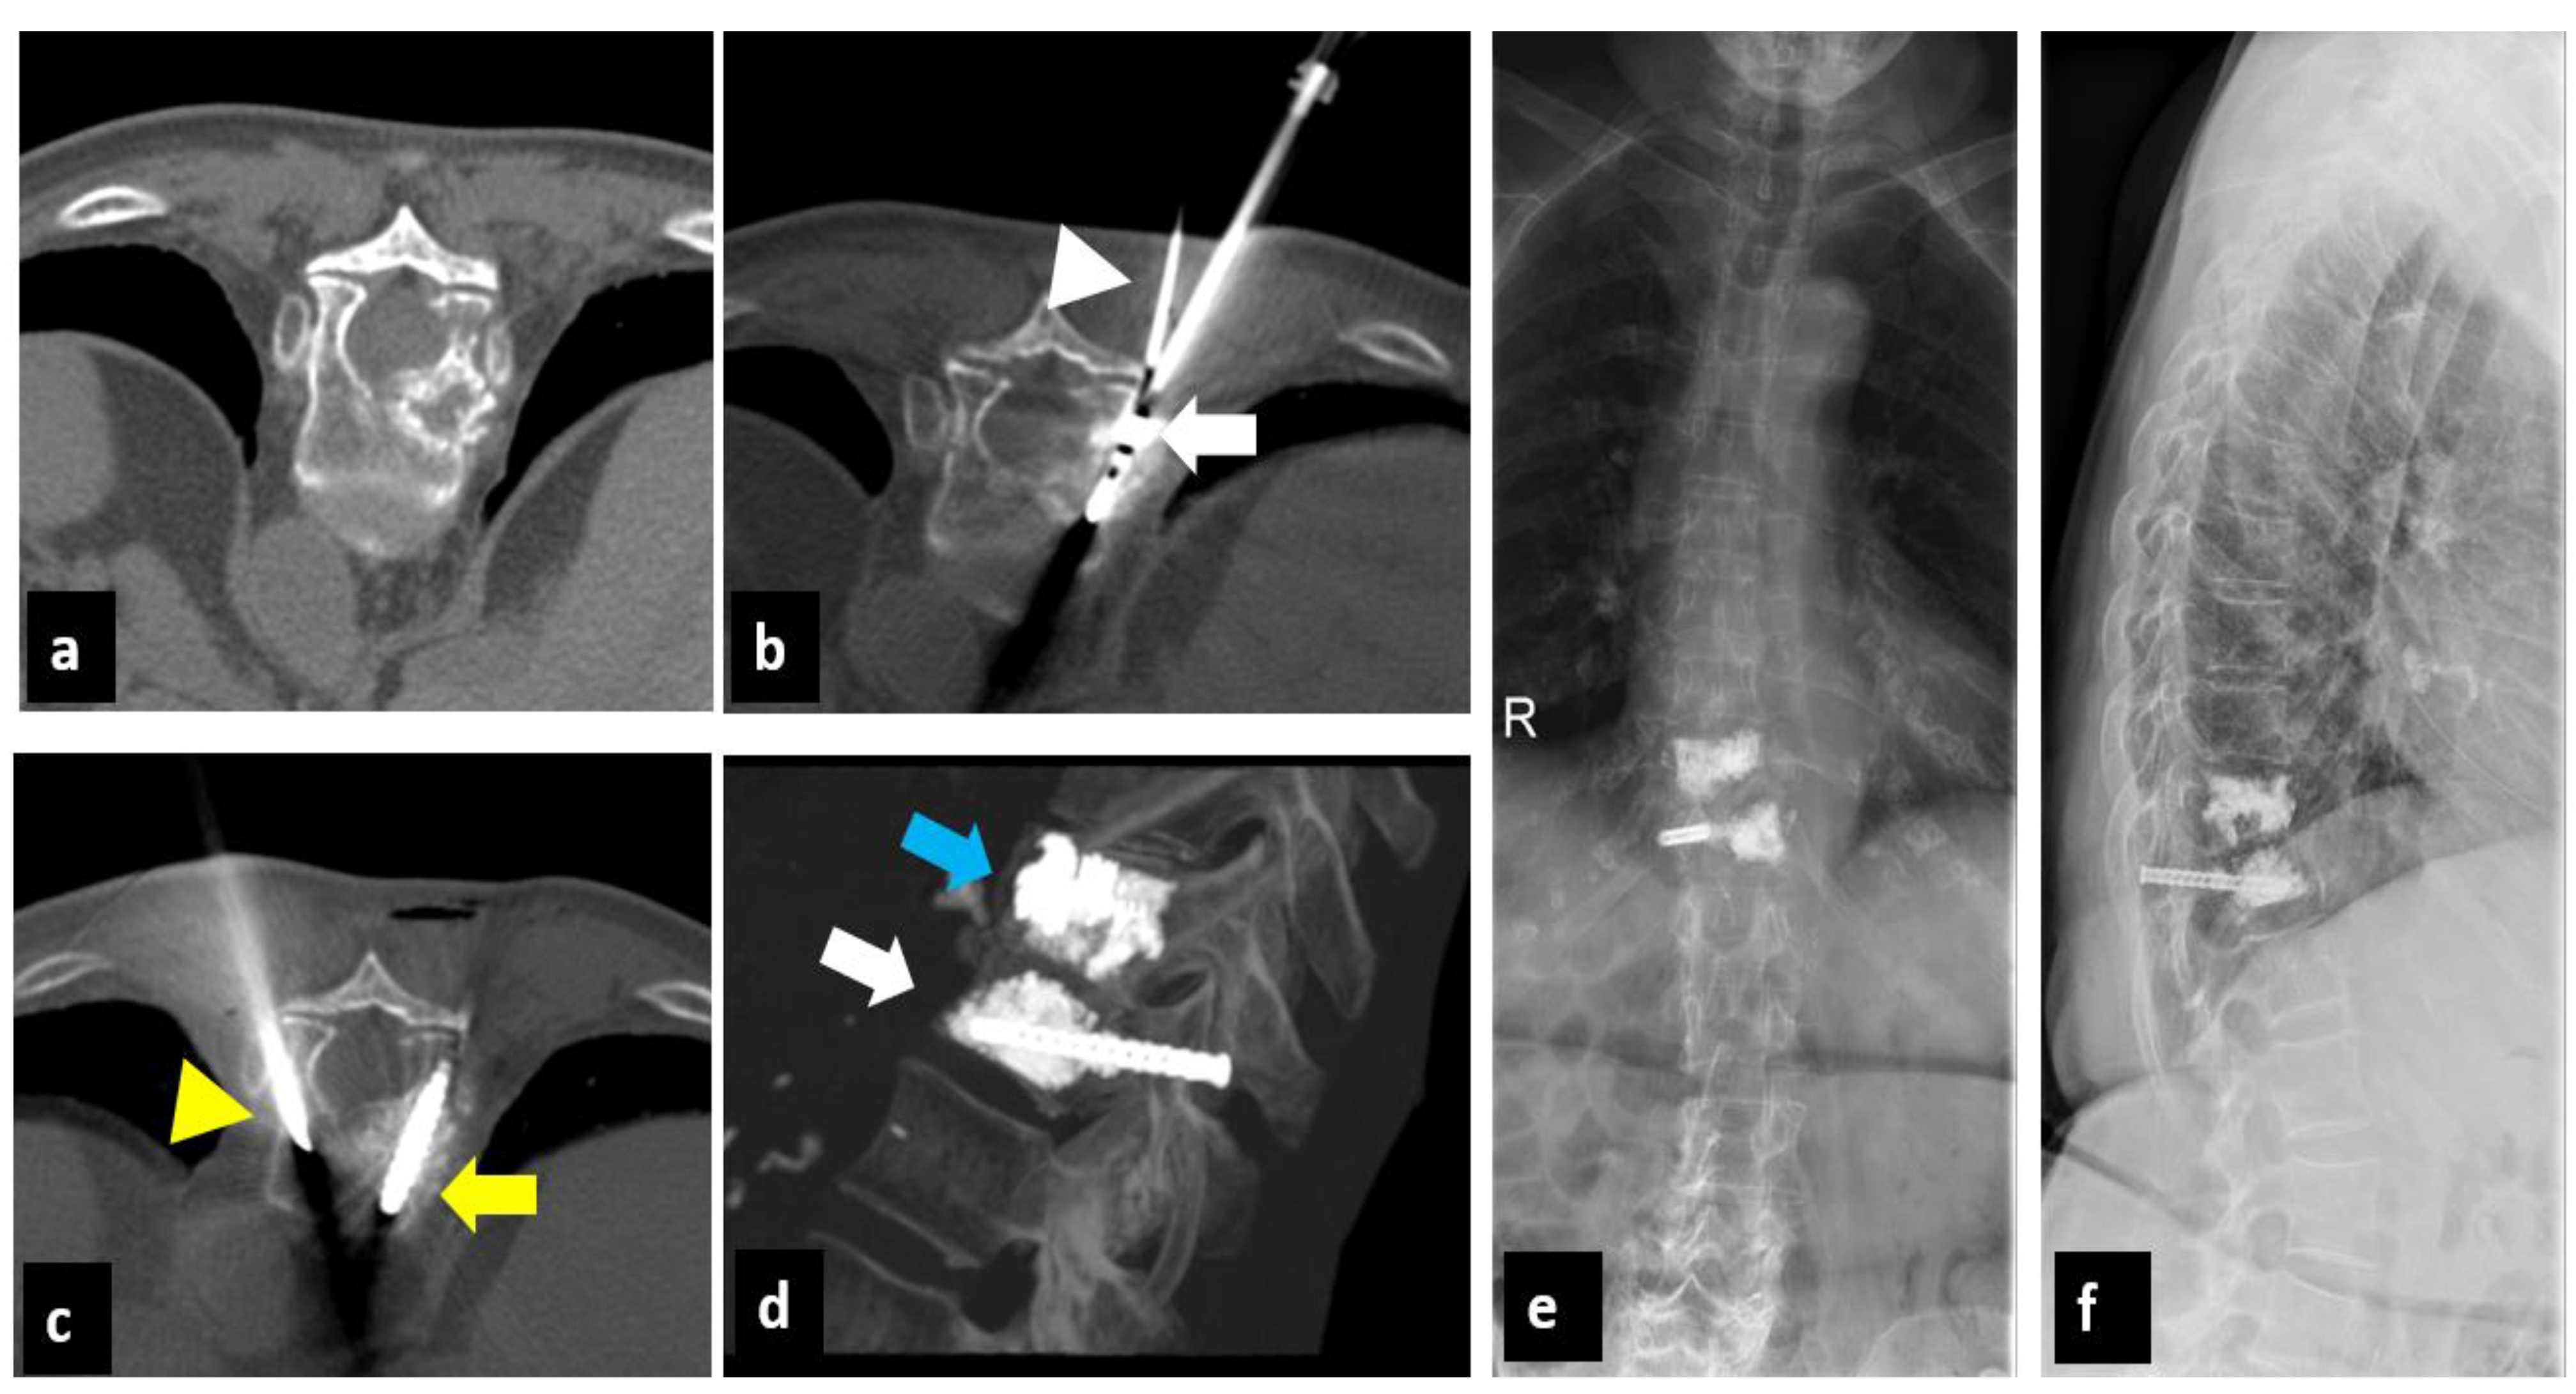

2. Materials and Methods

2.1. Treatment Technique

| 10 | 64 | breast cancer | L3 | 2 | 2 | 8/4 | 2/1 | 0/1 |